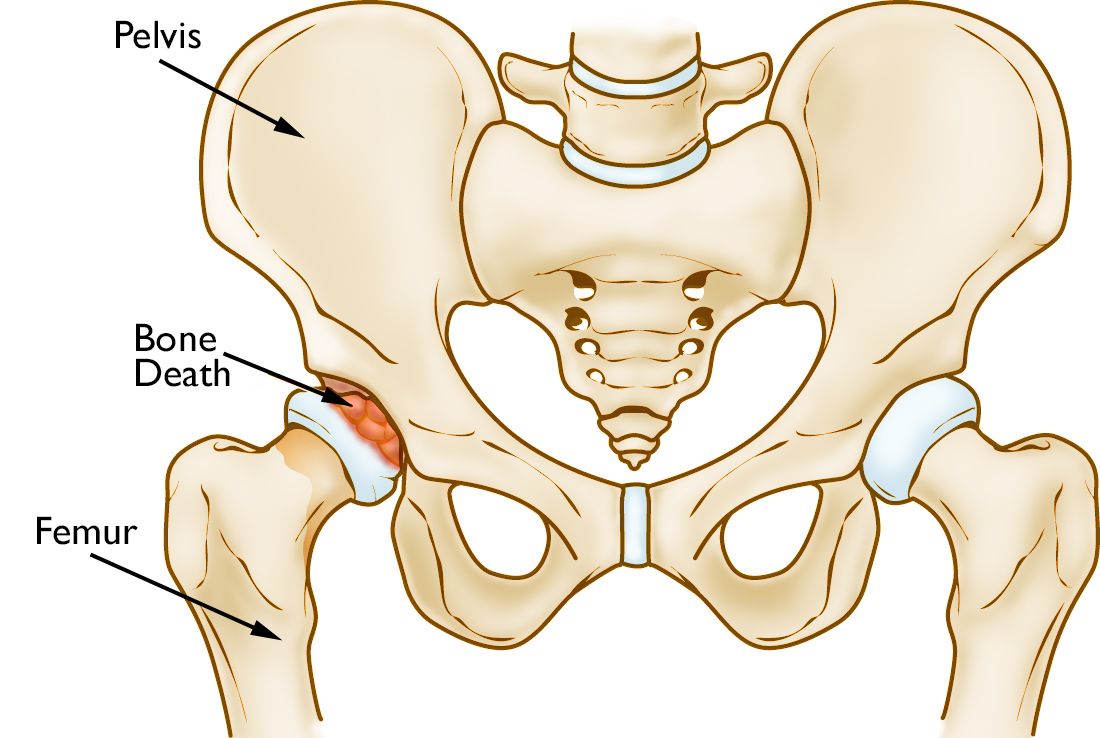

Osteonecrosis of the hip occurs in the femoral head, which is the ball of ball-and-socket hip joint.

Osteonecrosis of the hip

In osteonecrosis, the bone in the head of the femur slowly dies.